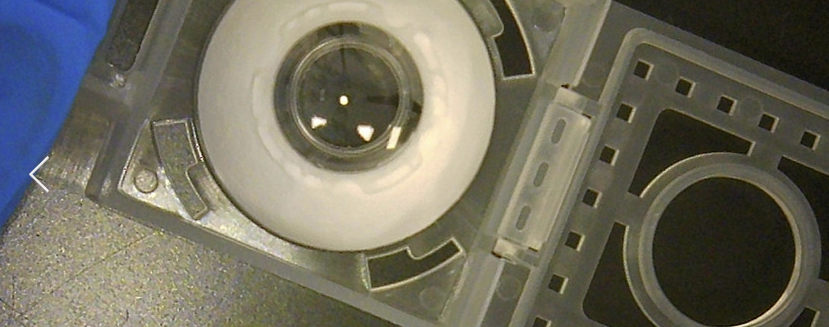

Η παραπάνω εικόνα δείχνει ακριβώς πώς λειτουργεί το εμφύτευμα. Η συσκευή μεταμοσχεύεται πλήρως μέσα στο τοίχωμα των ματιών. «Οι ινοβλάστες και το κολλαγόνο αποικίζουν σταδιακά την ενσωματωμένο εμφυτευμα με πλήρης ολοκλήρωση να επιτυγχάνεται εντός εβδομάδων, ενσωματώνοντας μόνιμα τη συσκευή στο μάτι του ασθενούς», σύμφωνα με την CorNeat Αυτό επιτρέπει βελτιωμένη οπτική οξύτητα και «εξαιρετικά γρήγορους χρόνους επούλωσης».